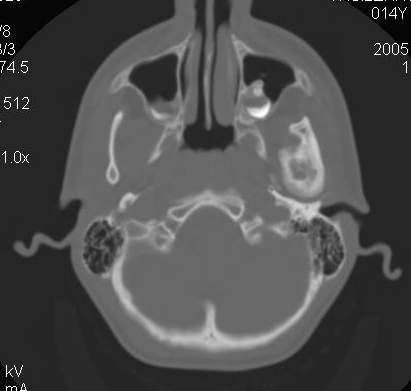

Пациент В., 13 лет. Диагноз: Костный анкилоз левого височно-нижнечелюстного сустава (ВНЧС), левосторонняя микрогения. Болеет с 2-х летнего возраста. Возможная причина развития анкилоза – воспалительный процесс (в первые 1,5 года жизни часто болел простудными заболеваниями, травму родители отрицают). В 3 и 5 лет проводилась редрессация – безуспешно.Прилагаются: ортопантомограмма, кадры СКТ с 3Д реконструкцией. Вопросы: определение тактики лечения – вид и сроки реконструктивно-пластической операции (этапов операции), а именно – неоартропластики и устранения микрогении, медикаментозная терапия в до- и послеоперационный период, ортодонтическое лечение.